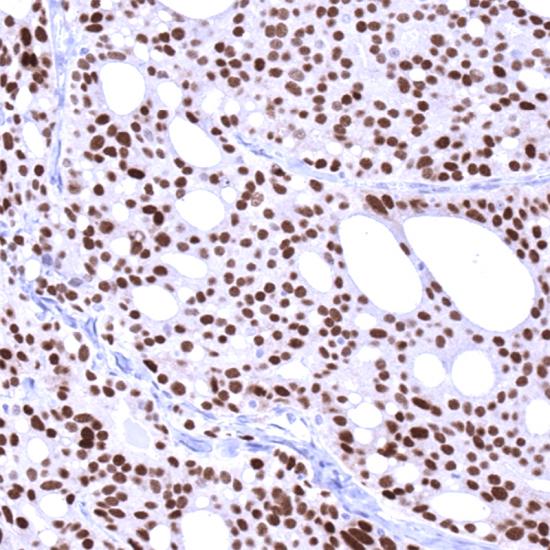

雄激素受體(Androgen Receptor,AR)抗體試劑(免疫組織化學(xué)法) 閩廈械備20190054號

• 陽性部位:

細(xì)胞核

• 陽性對照:

前列腺癌

雄激素受體的表達(dá)與組織分化程度相關(guān),分化好的前列腺腫瘤,雄激素受體比分化差的表達(dá)高。在前列腺癌患者中,雄激素受體是一個對激素有反應(yīng)性的標(biāo)志物。